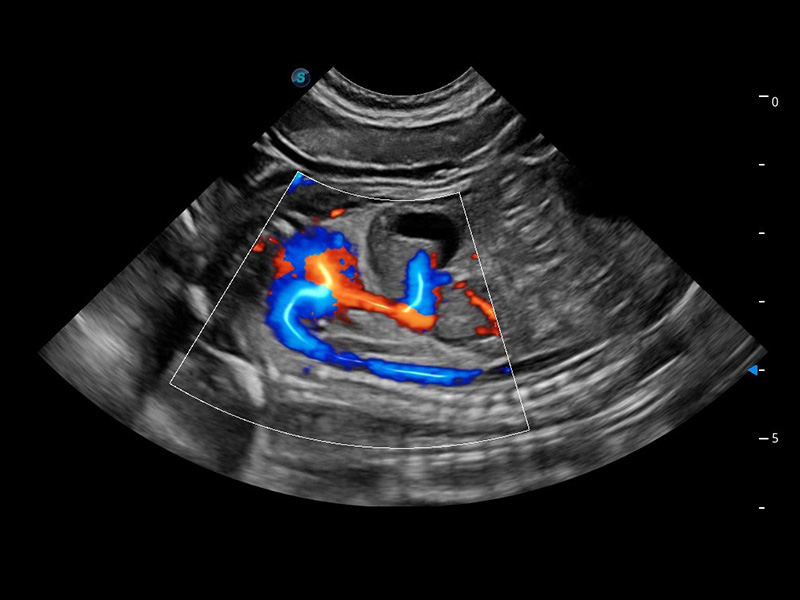

ProPet 60 作为一款高端台式动物超声设备,为动物医生的日常诊断提供了一系列贴合动物临床需求、解决临床实际问题的高级成像功能。凭借全系列高清探头,满足医生对腹部、心脏、生殖、浅表、肌骨等成像的所有需求,切实帮助您提升检查效率,提高诊断信心。

动物是人类最亲密的朋友和最值得信赖的伙伴。诸侯快讯官网也一直致力于探索动物专用的超声影像解决方案。 全新推出的ProPet系列,是诸侯快讯官网在动物超声影像智能化、专业化、精准化的一次跨越式革新。动物不能用言语来表述自己的不适,通过超声影像,ProPet系列搭建了动物医生与不同物种沟通的“桥梁”,为动物医生注入了“治愈之力”。